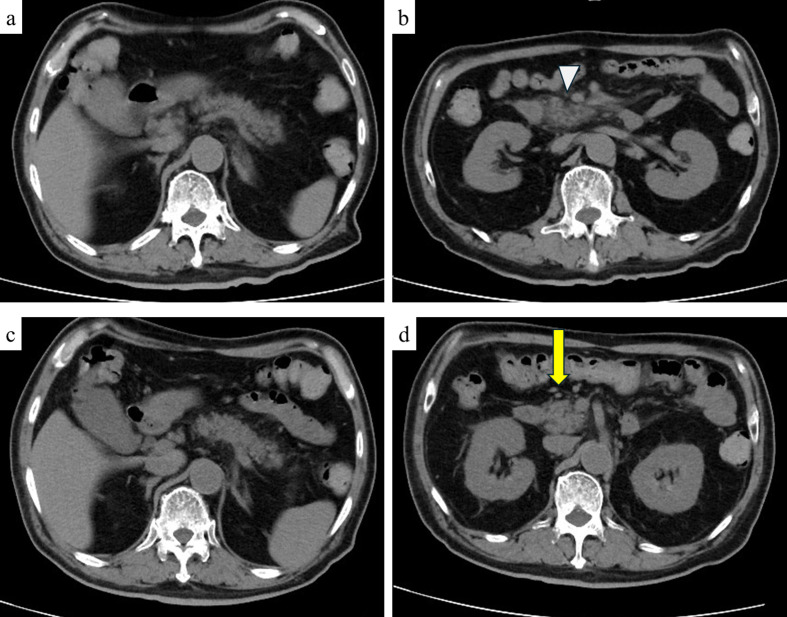

Objective: Since the onset of the coronavirus disease 2019 (COVID-19) pandemic, COVID-19 vaccination has substantially reduced mortality and hospitalization rates worldwide, with rare adverse events reported in clinical settings. Herein, we present a case of acute pancreatitis complicated by diabetic ketoacidosis (DKA) following the third COVID-19 vaccination dose. Patient: A 72-year-old male with a history of diabetes mellitus developed generalized fatigue, mild epigastric pain, nausea, and frequent vomiting after receiving the COVID-19 vaccine. Results: Blood analysis revealed elevated levels of pancreatic enzymes, hyperglycemia, and acidemia. Computed tomography revealed evidence of acute pancreatitis, leading to a diagnosis of both DKA and acute pancreatitis. Treatment with a large volume of saline and intravenous insulin improved both DKA and acute pancreatitis. After a thorough examination, no other factors capable of causing acute pancreatitis were identified. Hence, we concluded that acute pancreatitis was induced by COVID-19 vaccination. Conclusion: Acute pancreatitis is a rare but potentially life-threatening adverse event associated with COVID-19 vaccination. Delaying the treatment or diagnosis of acute pancreatitis can increase mortality risk in patients with both acute pancreatitis and DKA. Hence, it is crucial for healthcare professionals to consider the potential occurrence of acute pancreatitis and DKA following COVID-19 vaccination.